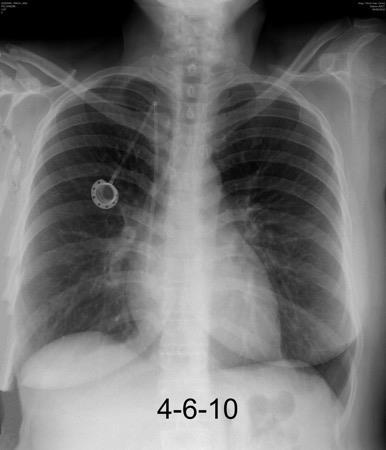

Pliegue axilar Normal

Rehúsa cirugía

2011. Acude por masa axilar

Linfoma NH de cél. B. Invasión Transtorácica.

Afectación axilar